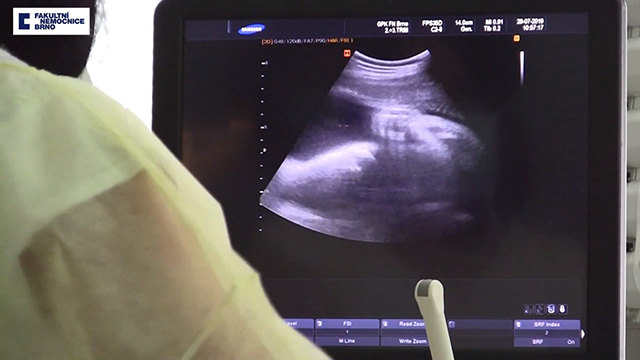

Theo trang New Straits Times, vào ngày 15.8 vừa qua, một bé gái được sinh ra tại bệnh viện Đại học Brno, nặng 2,13kg và cao 42cm. Người mẹ được xác định là đã chết não vào tháng 4, sau khi bị xuất huyết lúc mang thai được 16 tuần.

Các bác sĩ đã hỗ trợ cho người mẹ này cuộc sống nhân tạo nhằm giữ cho tim, phổi, thận và các cơ quan khác còn hoạt động trong khi theo dõi thai nhi. Trong suốt thai kỳ, bác sĩ siêu âm thường xuyên và làm các động tác như là người mẹ đang đi bộ, nhằm giúp em bé trong bụng phát triển bình thường.